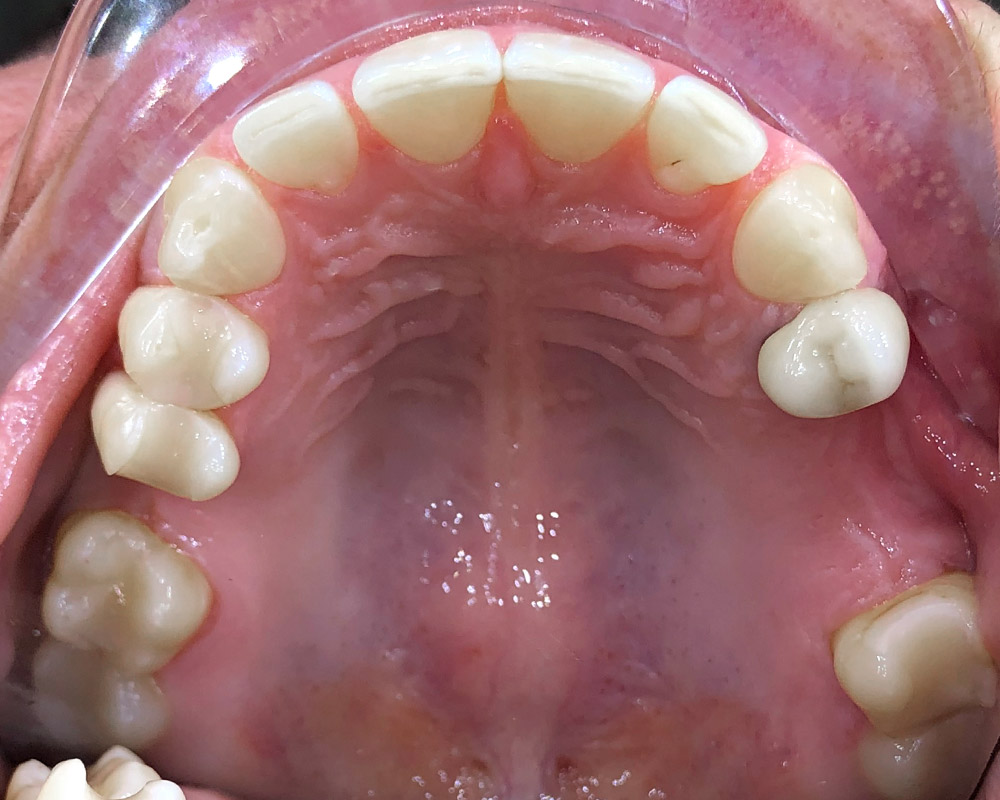

Кейс 23

Иванова Екатерина Сергеевна

Количество кап ВЧ 24

Количество кап НЧ 24

ДО

ПОСЛЕ